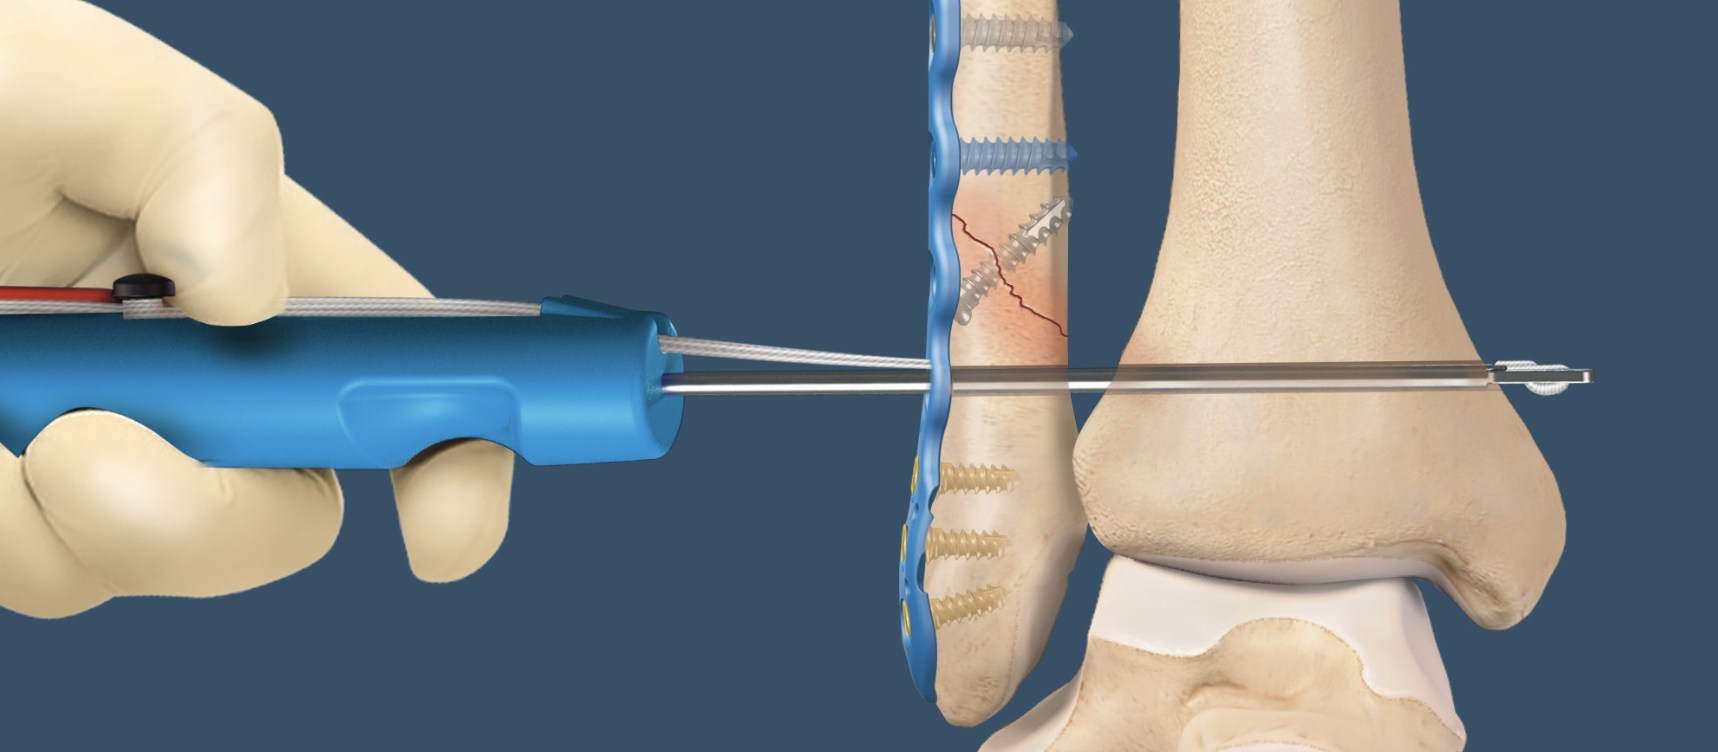

Suture button

Technique

Arthrex tightrope technique PDF

Arthrex surgical technique video

One or two suture buttons

- 1.5 - 3 cm above joint line

- angle 30 degrees anterior

- need to ensure entry point centered on fibula

- risk of saphenous nerve damage of medial side

- consider medial incision to identify and protect nerve

- talus at neutral dorsiflexion when tightening

One versus two buttons

- one versus two suture buttons in 40 patients

- no difference in outcome

- two suture buttons more costly